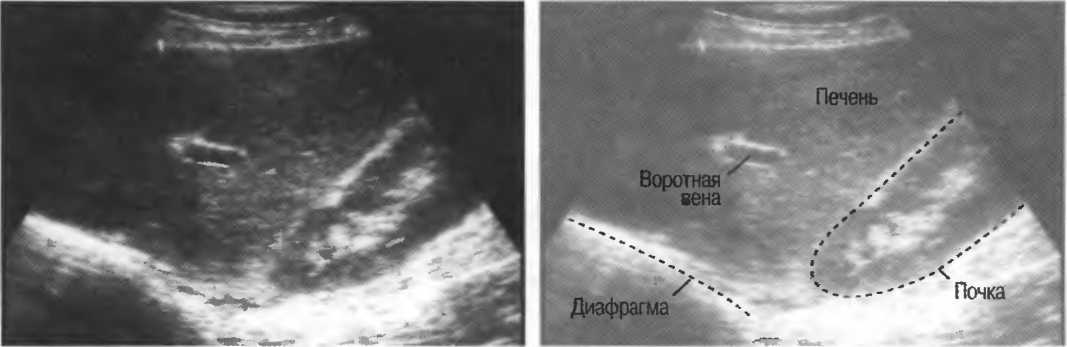

4. У здоровых обследуемых паренхима печени должна быть немного более эхогенна. чем кора рядом расположенной почки (рис. 26).

Рис.26. Продольный срез через печень и правую почку: нормальная паренхима печени более эхогенна, чем паренхима нормальной почки. Это еще один способ проверки качества изображения.